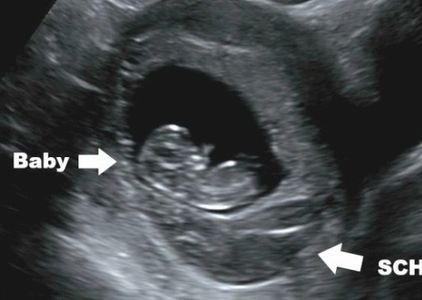

This involves formation of a visible gestational sac by 5 menstrual weeks (3 weeks post conception), a yolk sac, and a living (viable) embryo that should be evident by 6 weeks 4 days (4 weeks 4 days post conception). See below.

By the time we see the embryo, we should see a heart beat. Occasionally, we can see a tiny embryo but the heart beat is not definite until a few days later- this only happens with tiny embryos less than 6 mm in size (and usually 2-3 mm). In the case of an 'empty gestational sac' without a detectable embryo, we can rely on internal morphology of the gestational sac, and the size of the gestational sac rather than dates alone. A living embryo is usually seen when the gestational sac is 12-15 mm in mean diameter and should always be seen when the sac reaches 25 mm (in my experience, 20 mm with transvaginal scans). Unless findings are certain, we always assume the pregnancy is potentially viable until proven otherwise, and a followup scan is recommended. Both the embryo and the gestational sac should grow about 1 mm per day, so that a normal, viable pregnancy grows very quickly and is quickly distinguished from a non viable pregnancy. If the pregnancy is not viable, you should remember 6 things below.

What we will see by ultrasound in the First Trimester

2. By 5 menstrual weeks (3 weeks post conception), the gestational sac is very recognizable by ultrasound. We can start to see the gestational sac a few days earlier, when it is 2-3 mm in diameter, but should always see it by 5 weeks when the sac should be 5 mm.

3. Very soon after seeing the gestational sac, we will see the yolk sac. It helps provide nutrients to the early embryo and is the first site of red blood cell production.

4. By 4 weeks after fertilization (6 menstrual weeks), the tiny developing embryo will be visible with the first heartbeat seen by ultrasound. We should always see a living embryo by 6 weeks 4 days (4 weeks 4 days after conception). However, remember that your dates may not be as correct as you think they are. Even when you are certain, conception can occur several days after sexual intercourse.

Bleeding is common. It almost always arises from the placenta or placental margin (occasionally from the cervix). Placental bleeding may or may not form a subchorionic hemorrhage (SCH). Subchorionic hemorrhage may be very small and hard to visualize, or very large- even larger than the pregnancy. Older blood appears dark by ultrasound, more recent bleeding appears echogenic (brighter).